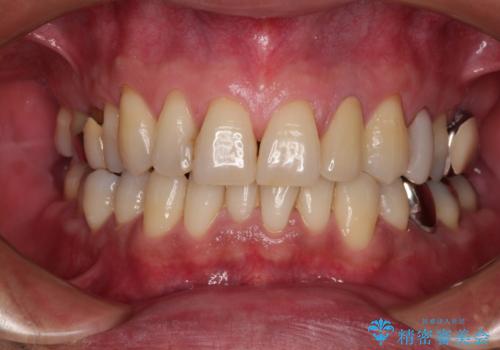

根管治療の土台のまま放置してしまった前歯 オールセラミッククラウンによる補綴治療

見た目の改善はもちろんですが、ものが挟まらなくなったり、舌触りが良くなったりと、口腔内の状態が改善されました。